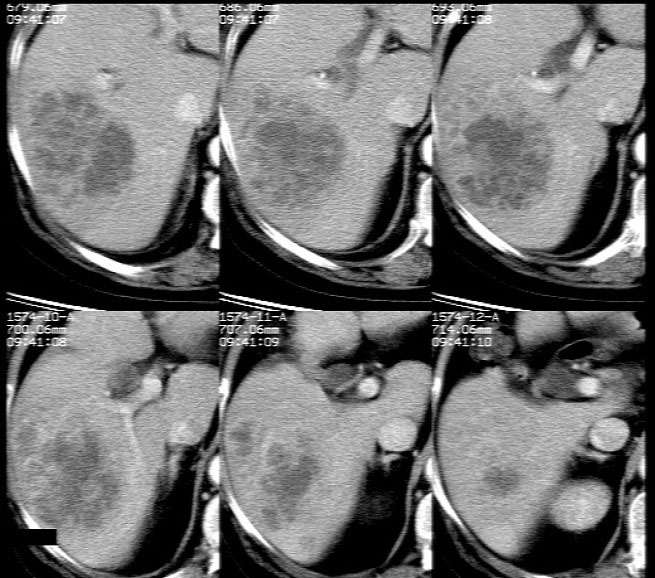

平扫示: 肝右后叶见团状低密度灶,边界欠清,密度略不均匀,ct值28-32hu,肝内胆管无扩张。

ct增强扫描示: 动脉期肝右后叶团状低密度边缘明显不均性强化,内呈不规则峰窝状低密度(无强化区),不规则分隔亦见明显强化;三期扫描像均见,病灶有明显占位征,周围血管、胆管推挤外移,病灶与正常肝组织分界不清,延迟期病灶周围见雾状略低密度(较肝左叶)。

肝右后叶团状低密度占位性病变,结合临床提示: 1、肝脓肿? 2、不排除肝ca可能。建议afp检查。

平扫示肝右后叶见团状低密度灶,边界欠清,密度略不均匀,ct值28-32hu,肝内胆管无扩张。ct增强扫描动脉期肝右后叶团状低密度边缘明显不均性强化,内见多发斑片状无强化液化区,呈不规则峰窝状。

考虑肝脓肿早期(蜂窝组织炎阶段)。

鉴别:肝血管瘤,早期周边强化明显,逐渐向中心充填。原发性肝癌,强化一般呈快进快出,多有乙肝肝硬化病史。